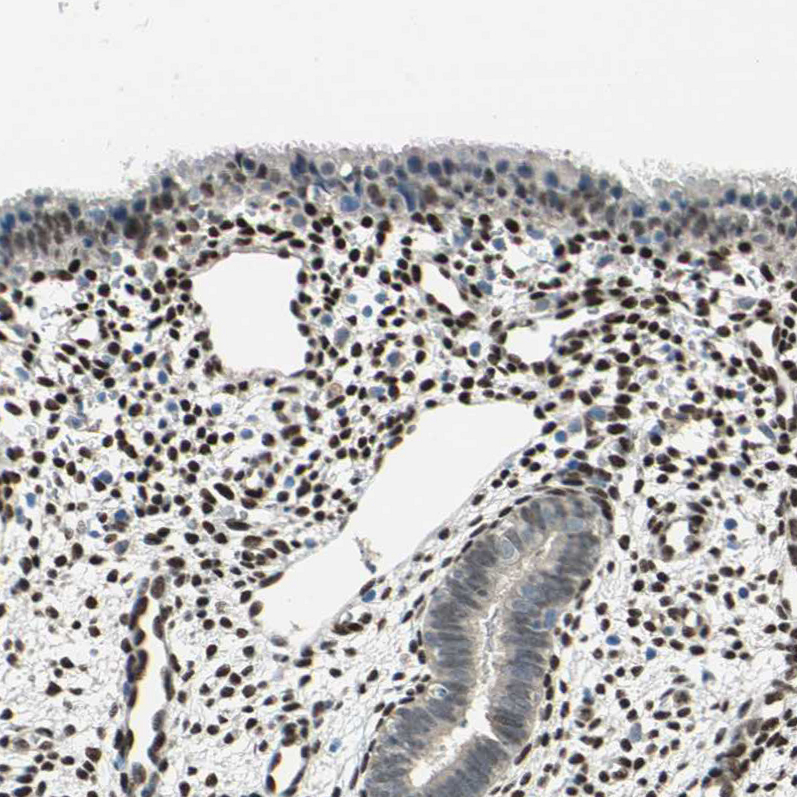

Immunohistochemistry analysis in human endometrium and pancreas tissues using HPA006240 antibody. Corresponding RBFOX2 RNA-seq data are presented for the same tissues.